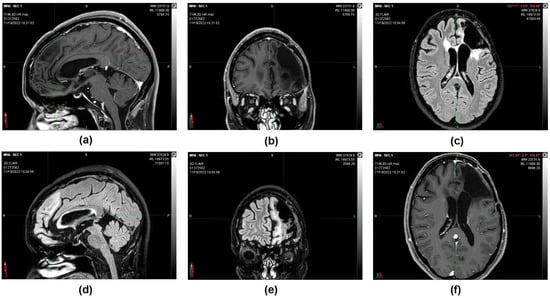

During the follow-up, quarterly visits, clinical-instrumental checks, and monthly blood and biochemistry tests were carried out. At the end of the first cycle of O2O3 therapy (9 February 2017), the 2 cm residual tumor mass that was present 3 months before was no longer visible on the brain magnetic resonance imaging (MRI) (Figure 3), and the stable-negative tumor mass was confirmed with the MRI on 11 October 2022 (Figure 4).

Figure 3.

(a,c) 12 October 2016, CT scan image with contrast medium. Posterior to the surgical cavity, an approximately 2 cm hyperdense solid nodule is present (b) 9 February 2017, MRI T1 sequence with contrast medium. After the first cycle of O2O3 therapy, the 2 cm residual tumor mass that was present 3 months before was no longer visible (d) 9 February 2017, MRI image sequence in Fluid-attenuated inversion recovery (FLAIR).

Figure 4.

11 October 2022, instrumental examination, stable negative picture. (a,b,f) MRI images, T1 sequence with contrast medium. (c–e) MRI images, sequence in FLAIR. The morphological picture remained stationary—the T2 hyperintensity surrounding the known left frontal malacic cavity extended to the knee and right root of the corpus callosum and in the left semioval center and was without mass effect and not modified in the contrastographic phases. Non-focality of new onset at the remaining levels. In the spongiosa of the left frontal bone in the median region and on the profile of the operculum, there are two areas of altered signal with contrastographic impregnation, both of which are stationary. The median structures are on an axis. The ventricular cavities and subarachnoid spaces are overlapping in size and morphology.